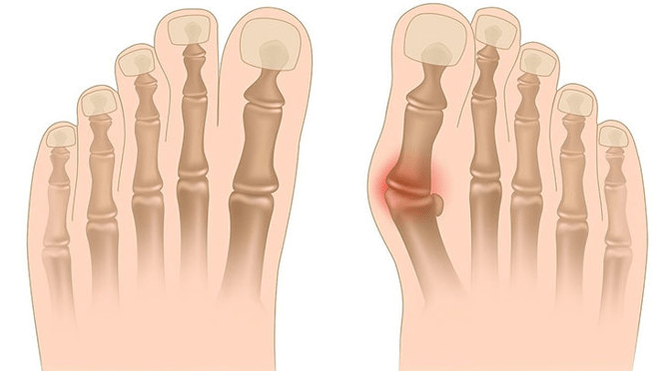

Valgus deformasyonu, uzunlamasına kemerinin düzleşmesi ile karakterize edilen ayağın eğriliğidir. Tipik olarak, ayağın iç kenarı indirilir (“damlalar”) ve topuk ortaya çıkar.

Ayakları aldığınızda (onlara arkadan bakarsanız), ayak bileği seviyesinde X benzeri bir deformasyon oluşur: ayak bilekleri temas halindeyken, topuklar birbirinden 5-6 santimetre mesafededir.

- I - Kemik deformasyonu yoktur, ağrı ayak bileğinin iç yüzeyinde belirlenir (posterior tibial kasın sabitlenmesi alanında);

- II - Hafif eğrilik, topuk hafifçe reddedilir;

- III - Ayak ayrılır ve deformasyon sabitlenir (doğru şekilde düzeltilmez);

- IV - eğrilik sadece ayakta değil, aynı zamanda ayak bileği ekleminde de gözlenir.

Hastalığın bir sonraki aşaması, ayağın eğriliğinin ortaya çıkmasıyla ilişkilidir: ayakta durma pozisyonundaki hastalar ayağın dış kenarına değil, tüm bölgesine güvenir. Yürüyüşte hafif bir değişiklik gözlenir.

Üçüncü aşamada, çözünmüş kemiğin çıkıntısı belirlenir (ayak bileğinin iç yüzeyindeki ayak bileğinden belirgin şekilde daha düşük) ve ayrıca dışarıdaki topuğun güçlü bir yönlendirilmesi (hasta topuk kemiğinin iç kenarına dayanır).

Ayakların gelişmiş valgus deformasyonu, hem ayağın hem de ayak bileği ekleminin belirgin bir eğriliği ile karakterizedir. Hastalar alt bacağın kaslarında yanma ağrısının yanı sıra önemli bir yürüyüş ihlali şikayet ediyorlar: Dizler birbirine ovalarken, sağ ve sol ayak bir mesafede bulunur.